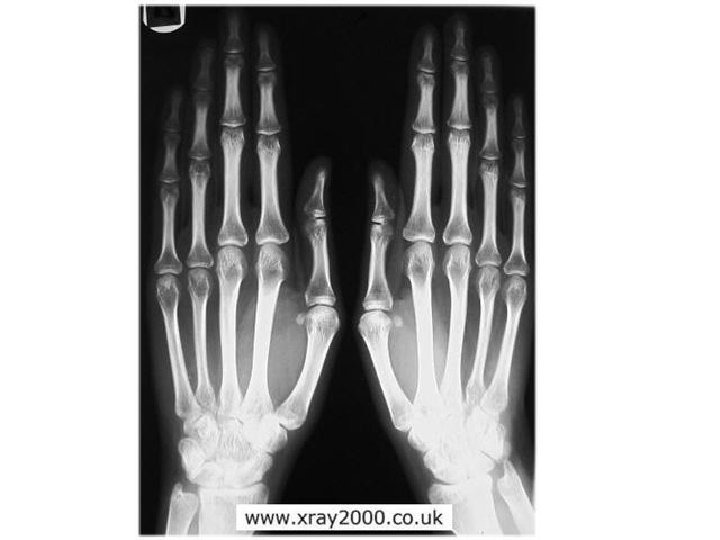

Bones of the Human Body · The skeleton has 206 bones · Two basic types of bone tissue · Compact bone · Homogeneous · Spongy bone · Small needle-like pieces of bone · Many open spaces Copyright © 2003 Pearson Education, Inc. publishing as Benjamin Cummings Figure 5. 2 b

Bones are classified by their shape: 1. Long- bones are longer than they are wide (arms, legs) 2. Short- usually square in shape, cube like (wrist, ankle) 3. Flat- flat , curved (skull, Sternum) 4. Irregular- odd shapes (vertebrae, pelvis) 5. Sesamoid-also a short bone (patella)